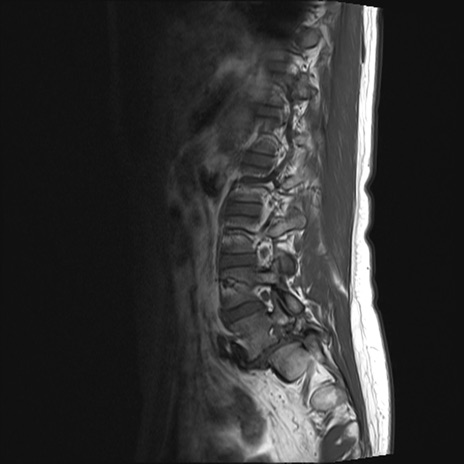

【整形】TIPS症例4 腰椎MRI T1WI(矢状断像)

腰椎MRI

T2WI(矢状断像)